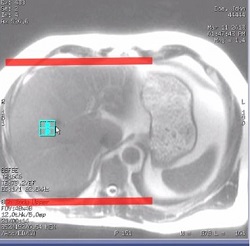

Figure 1. Red box indicates appropriate localizer FOV position that excludes shoulders